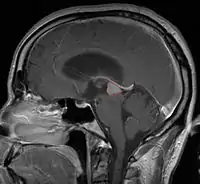

Pineal Gland Tumors

- Determined by the spatial anatomy and direction of growth

- Obstruction of aquaduct: hydrocephalus presenting as headaches, nausea, vomiting

- Compromise of superior colliculus: vertical gaze palsy, pupillary and oculomotor nerve paresis (Parinaud syndrome)

- CSF diversion may be necessary in patients symptomatic from obstructing hydrocephalus, although if open surgery is done, may not be necessary

- Usually well-circumscribed, large lesions, sometimes with cystic component